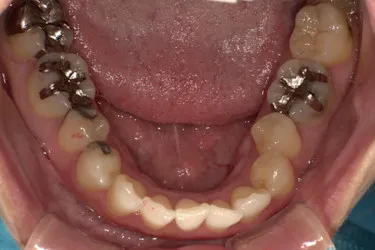

ホワイトニングも同時並行で行い、「毎週自分の歯並びの写真を撮っていたので、綺麗になっていくのが楽しみだった」という矯正体験について45歳主婦のN.T.様にお話を伺いました。

毎週自分で歯並びの写真を撮っていたので日々綺麗になっていく歯並びを見るのが嬉しく、家族からも綺麗になったねと言われました! マウスピース矯正と並行してホワイトニングも行っていたので、歯が格段に綺麗になるのを実感できたのが嬉しかったです。